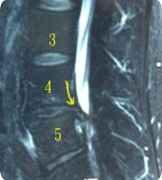

林先生磁振造影檢查有嚴重的第4-5腰椎間盤退化,並向後下方突出,壓迫了神經根,脊管內的脊髓液及神經。

磁振造影檢橫切面 可見突出的椎間盤,向後下方位移至第五 腰椎體後方

後註: 林先生的椎間盤突出並向下位移,是屬於內視鏡手術 中困難不易成功的病例,我們將突出的椎間盤全部取出,術後原有的症狀完全解除。林先生及本站其他感謝函,未經修改一字,全文刊登。